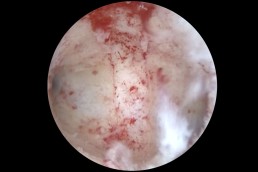

Histeroscopia reprezintă o etapă importantă în cadrul investigațiilor efectuate pacientelor ce prezintă diagnosticul de infertilitate. Histeroscopia poate identifica modificări subtile ale cavității uterine, ce nu pot fi diagnosticate prin ecografie, ceea ce face ca această inervenție să devină extrem de utilă la pacientele cu infertilitate. Un exemplu poate fi reprezentat de inflamația cronică a endometrului, situație numită endometrită (Fig. 9, 10).